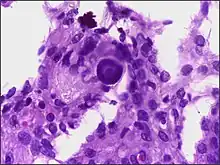

Pathophysiology

- A woven architectural pattern

- Psammoma bodies (spheroid calcifications)

- Syncytial cells (having indistinct cell membranes) with eosinophilic (pink) cytoplasms

- Round uniform nuclei

- Whorls (concentric cell arrangements)[15]

Meningiomas arise from arachnoidal cap cells,[16] most of which are near the vicinity of the venous sinuses, and this is the site of greatest prevalence for meningioma formation. Some subtypes may arise from the pial cap cells that migrate during the development together with blood vessels into the brain parenchyma.[17] They most frequently are attached to the dura over the superior parasagittal surface of frontal and parietal lobes, along the sphenoid ridge, in the olfactory grooves, the sylvian region, superior cerebellum along the falx cerebri, cerebellopontine angle, and the spinal cord. The tumor is usually gray, well-circumscribed, and takes on the form of the space it occupies. They usually are dome-shaped, with the base lying on the dura.

Histologically, meningioma cells are relatively uniform, with a tendency to encircle one another, forming whorls and psammoma bodies (laminated calcific concretions).[18] As such, they also have a tendency to calcify and are highly vascularized.